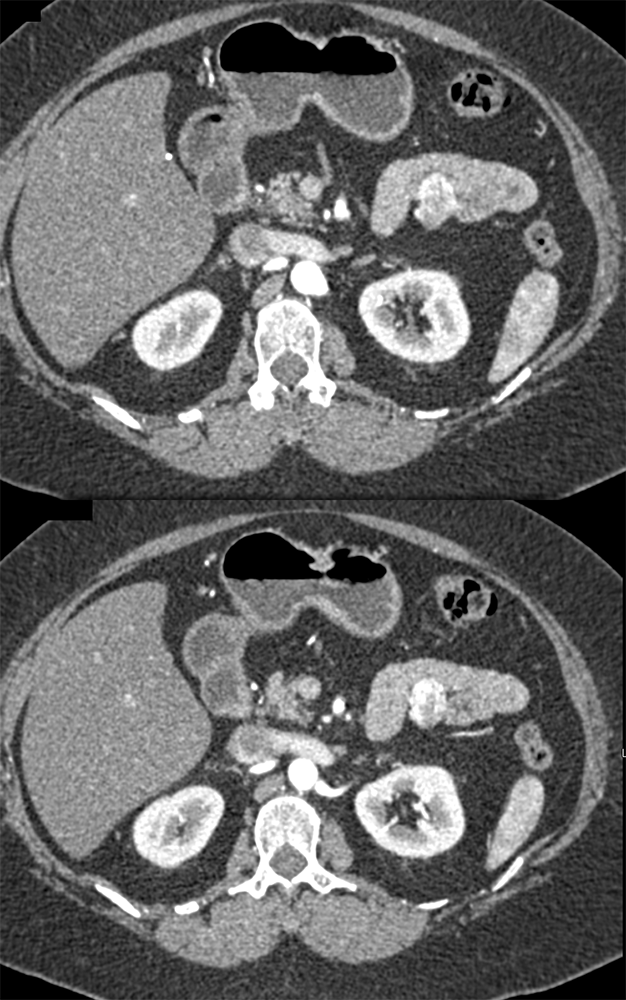

RCC Metastatic to Small Bowel ![]() |

![]() |